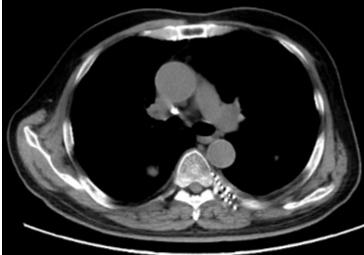

胰腺癌引起的腹痛患者,男性,65岁,确诊为晚期胰腺癌,疼痛剧烈,体位受影响,喜欢呈大虾一样蜷缩状,影响睡眠和日常活动。尽管使用了阿片类药物,但疼痛控制仍不理想。给予CT引导下腹腔神经丛神经毁损术后,患者的疼痛评分从8分降至3分,阿片类药物的使用量减少50%,生活质量显著提高(图2)。

图2:CT引导下腹腔神经丛毁损术